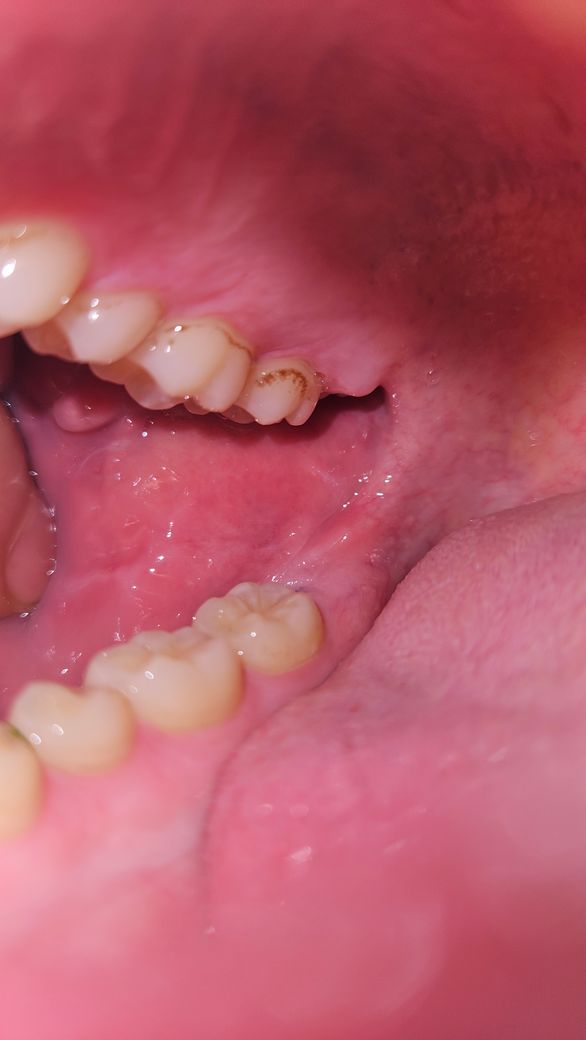

치아안쪽 검은색 점들, 충치인가요 치석인가요?

어느날 치아 안쪽 검은 점들이 눈에 들어오기 시작했는데요

하루 3-4번 양치꼬박꼬박 하고 있는데

잘 안닦이는 부위라 치석이 생긴건지

충치인건지 사진보고 판단해주시면 감사하겠습니다!

특별히 아프거나 하지는 않습니다

• 1번 째 사진

사진으로만 봤을 경우에는 단순한 착색으로 보입니다.

하지만 정확한 확인을 위해서는 직접 진료를 받아 보는것이 좋습니다.

충치도 치석도 아니고 그냥 착색입니다. 착색자체만으로 치아나 잇몸에 영향을 주지는 않지만 착색이 붙어있으면 치아표면이 울퉁불퉁해서 치태가 잘 달라붙고 치석이 되기 쉽기도 합니다. 그렇다고 너무 걱정하실 필요는 없고 양치질 구석구석 깨끗이 하시고 주기적으로 때되면 스케일링 받아주시면 됩니다. 양치가 덜 되는 곳에 착색이 더 잘 생기기 때문에 그 부분을 평소에 좀 더 신경써서 닦아주시면 좋을 것 입니다. 그리고 아마 다른 치아들에도 같은게 생겼을 텐데 만약 눈에 보이는게 싫으시면 치과 가셔서 부분적으로 제거하실 수도 있습니다.

충치보다는 착색, 치석에 가까운 것으로 보입니다 해당 부위는 충치가 잘 생기는 부위는 아닙니다